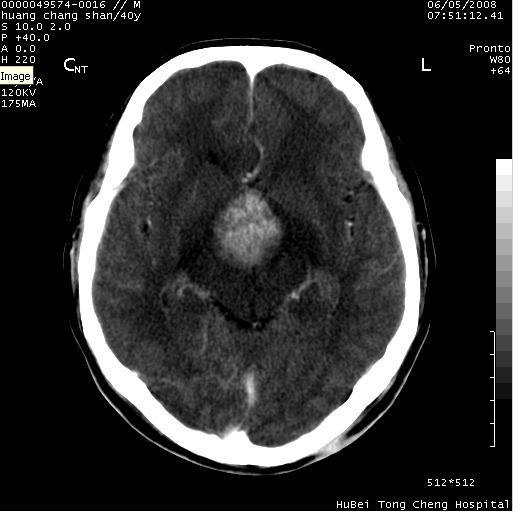

患者 m,40y。头痛,视力模糊,多饮多尿,性欲减退半年余。

行ct平扫+增强,图象如下:

肿瘤强化明显、鞍部骨质结构未见增大、破坏,考虑脑膜瘤可能性大

鞍背无破坏和明显受压,病变明显均匀强化,边界清晰。鞍上区脑膜瘤可能性大,不除外生殖细胞瘤。

平扫病灶呈等密度,增强后强化明显,均匀一致,结合病史首先考虑:垂体瘤。脑膜瘤不支持,因为脑膜瘤平扫多为实性呈均匀高密度影像,内分泌症状多不明显,垂体内分泌素测定正常。

鞍上池肿瘤,鞍背及垂体窝形态变化不明显,病灶强化密度均匀且高度强化,考虑实性颅咽管瘤、生殖细胞瘤及脑膜瘤可能。

结合临床考虑鞍上生殖细胞瘤可能性大于脑膜瘤(增强未见脑膜围征),建议结合冠状位扫描看病灶起源及垂体窝、鞍底情况。垂体窝内未见明显软组织密度影,垂体窝未见扩大,暂不考虑垂体瘤;病灶较大,未见囊变及钙化,颅咽管瘤不支持。期待结果!

1、头痛,视力模糊,多饮多尿,性欲减退半年余,提示:肿瘤为功能性肿瘤。

2、ct表现:肿瘤呈类圆形,均匀略高密度,无囊变,无钙化。侧脑室有扩大。

3、首先考虑:功能性垂体大腺瘤。

4、鉴别诊断:脑膜瘤,瘤体内点状钙化最具特征性,常位于鞍结节。颅咽管瘤,蛋壳样钙化,常有囊变。动脉瘤,位于鞍旁,强化与动脉一致。有时尚需与发生于鞍区的生殖细胞瘤鉴别,生殖细胞瘤钙化亦较常见。